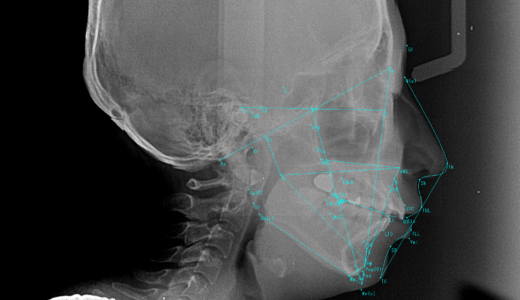

セファロ分析とは?矯正治療に必要な理由とレントゲン分析の基本